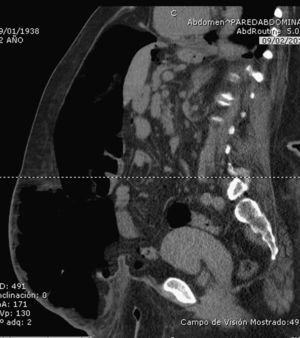

Se definió técnicamente una hernia o eventración abdominal con pérdida de domicilio como aquella en la cual más del 50% del contenido de la cavidad abdominal estuviera fuera de la misma (fig. 1). Esto fue determinado en casi todos los casos por la realización de una TAC abdominal preoperatoria (fig. 2). Una vez seleccionados los pacientes, se remitieron para valoración preanestésica y se programaron para ingreso hospitalario previo a la intervención quirúrgica.

Al cabo de 2 semanas de insuflación, se examinó la pared abdominal, evaluando la tensión que presentaba la musculatura en la parte lateral del abdomen, para constatar que esta se iba relajando adecuadamente. En algunos casos se realizó un control tomográfico del paciente (fig. 4), pero no de manera sistemática, ya que el seguimiento de la evolución fue principalmente clínico, considerando al paciente apto para la intervención cuando la musculatura lateral del abdomen se encontraba completamente distendida.